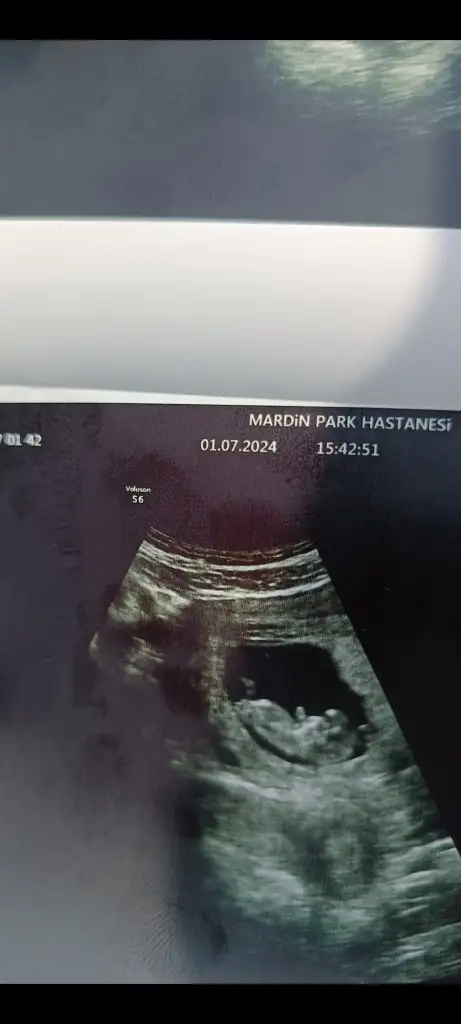

Merhaba burada nub u. Göremedim ki tamKartanesi biz 9. Haftadayız ama benim için de bir tahminde bulunur musun

Anladım daha küçüğüz biraz büyüyünce tekrar gönderirim teşekkür ederim çokMerhaba burada nub u. Göremedim ki tam

Kartanesi merhaba bugün kontrolüm vardı ama görebilecek misin bir tahminin var mıMerhaba burada nub u. Göremedim ki tam